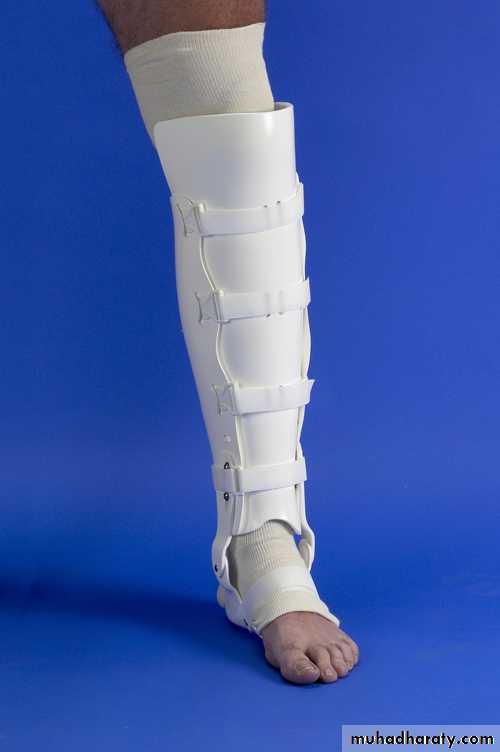

In fresh fractures of both bones of the leg, attention should be concentrated solely on the fracture of the tibia. The fibular fracture may be disregardedConservative treatment by reduction and P.O.P followed by functional cast brace, and this is the method of choice whenever it is practicable. The holding of the fracture is retained until the tibia fracture is firmly united as shown by clinical and radiographic examination usually a matter of between 3 and 4 months. Thereafter active exercises are carried out under the supervision of a physiotherapist to restore a full range of knee, ankle and foot movements.

Functional brace